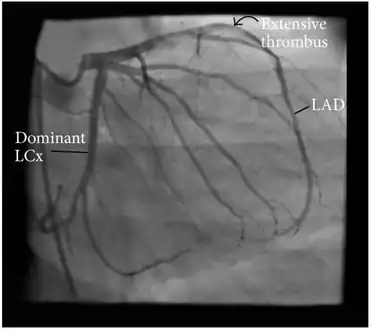

Angiographic image showing extensive LAD thrombosis

Coronary angiography of an MI patient